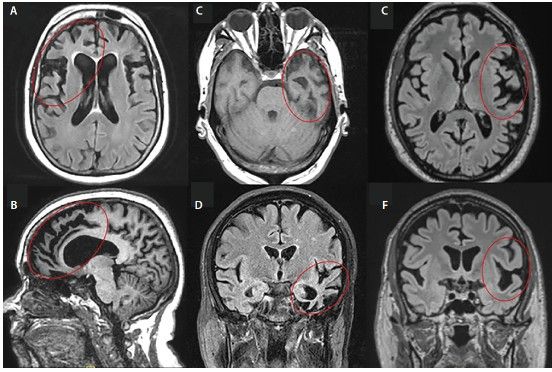

С помощью МРТ можно диагностировать ЛВД и исключить другие болезни, такие как опухоли или цереброваскулярные заболевания, например атеросклероз. Однако точный диагноз на основании осмотра и МРТ можно поставить только примерно в 60 % случаев [44].

При описании снимков врач обратит внимание на наличие атрофии в отдельных участках — передней части островка и поясной извилины, орбитофронтальной, дорсолатеральной префронтальной и передней височной доли.

![МРТ при ЛВД: А, Б — пЛВД; C, D — сППА; E, F — аППА [70] МРТ при ЛВД: А, Б — пЛВД; C, D — сППА; E, F — аППА [70]](/media/bolezny/lobno-visochnaya-demenciya/mrt-pri-lvd-a-b-_-plvd-c-d-_-sppa-e-f-_-appa-70_s.jpeg)

МРТ при ЛВД: А, Б — пЛВД; C, D — сППА; E, F — аППА [70]